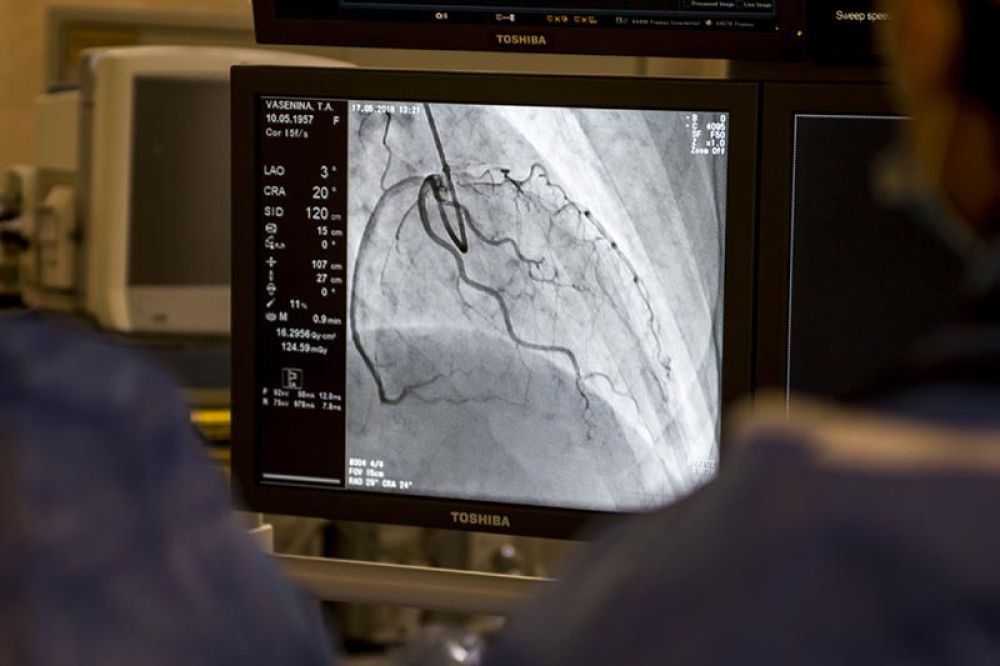

Классическая коронарография – исследование кровеносных сосудов сердца (коронарных артерий), которое проводят рентгенэндоваскулярные хирурги. Когда необходимо такое исследование, в чем его особенности, почему коронарографию делают строго по показаниям, рассказывает кандидат медицинских наук Денис Витальевич Фетцер, заведующий отделением рентгенхирургических методов диагностики и лечения ГБУЗ « МКНИЦ Больница 52 ДЗМ», врач по рентгенэндоваскулярным методам диагностики и лечения, сердечно-сосудистый хирург.

«Ангио» переводится с греческого как «сосуд». Основная функция сосудов — снабжение органов кровью. Ангиография позволяет увидеть «проблемные участки» сосудов, для этого в просвет сосуда вводится контрастное вещество, отражаемое рентгеновскими лучами. Ангиограф — рентгенологическая установка, предназначенная для проведения исследований и процедур с использованием контрастного вещества и рентгеновского излучения. В операционной, оборудованной ангиографом, мы можем не только диагностировать поражения сосудов, но и проводить их лечение. Например, расширить суженный сосуд с помощью баллонной ангиопластики и установить (имплантировать) в него поддерживающий стент. В нашем отделении мы проводим диагностику и лечение сосудов при различных заболеваниях. Однако коронарография — одно из самых востребованных диагностических исследований, ведь коронарные сосуды отвечают за работу сердца. При обнаружении критически значимых поражений (существенного сужения или полной закупорки сосуда тромбом), можем тут же оказать пациенту высокотехнологическую помощь.

Основные показания к коронарографии — ишемическая болезнь сердца со стенокардией высокого функционального класса (то есть возникающая уже при малой физической нагрузке), у пациентов с выраженными нарушениями ритма сердца, острым коронарный синдромом (инфаркт миокарда, «прединфарктное» состояние), обследование перед некоторыми хирургическими операциями на сердце или, например, трансплантацией органов. Коронарография позволяет оценить степень поражения коронарных артерий, определить, насколько сужен внутренний просвет, есть ли участки полного закрытия (окклюзии) артерии. При коронарографии мы хорошо видим «анатомию поражения», что дает возможность, с учетом данных других обследований, принять обоснованное решение о том, нужно ли хирургическое лечение, и если да, то какие методы лучше использовать.

Пациенту же с острым инфарктом требуется экстренная помощь. С помощью коронарографии мы определяем участки, на которых нарушено кровоснабжение, или артерии, полностью закрытые тромбом. Это жизнеугрожающая ситуация, мы сразу переходим к восстановлению кровообращения с помощью баллонной ангиопластики и последующей имплантации коронарного стента.